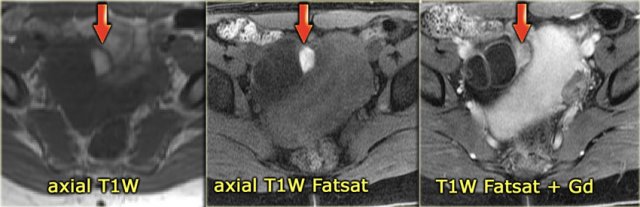

Endometrioma Endometrioma

The next case is a unilocular, mildly hypoechoic ovarian lesion with through transmission.

There is no internal or wall vascularity on Doppler.

On ultrasound this can again either be a hemorrhagic cyst or an endometrioma.

Continue with the MR images

6 months later a follow-up MRI was performed.

The lesions are bright on T1-weighted images.

The bright signal persists on fat saturation indicating the presence of blood.

There is T2 shading consistent with a hemorrhagic lesion.

There is no enhancement.

The fluid-fluid level in the right ovarian lesion also confirms its cystic nature.

The fact that the lesions persist after 6 months makes bilateral endometrioma much more likely than hemorrhagic cysts.